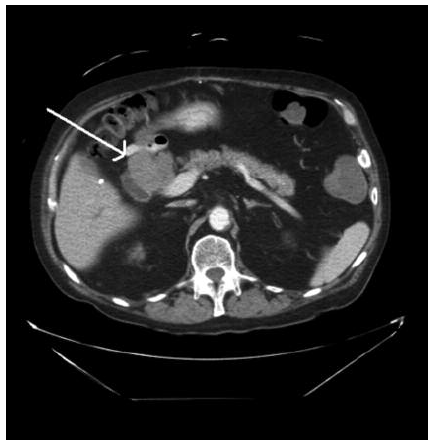

Endoscopic retrograde cholangiopancreatography is crucial to the evaluation of jaundice following liver transplant. We report a case of recurrent hepatocellular carcinoma 15 years after orthotopic liver transplant, presenting initially as obstructive bile duct compression as detected by cholangiogram(Figures 1 and 2). Laparotomy revealed hepatocellular carcinoma invading the common bile duct.

The physical examination was unremarkable except for icteric sclera. The patient’s laboratory values were as follows: total bilirubin level, 220.642 µmol/L (normal range, 5.0-21.0 µmol/L); alkaline phosphatase, 19.305 µkat/L (normal range, 0.5-2.0 µkat/L); aspartate aminotransferase, 5.318 µkat/L (normal range, 0.17-0.51 µkat/L); alanine aminotransferase, 6.296 µkat/L (normal range, 0.17-0.68 µkat/L); gamma-glutamyltransferase, 4.334 µkat/L (normal range, 0.03-0.51 µkat/L); and alpha fetoprotein, 36.8 µg/mL (normal range, 0-20 µg/mL). The results of a complete blood count were within normal limits. Computed tomography scanning revealed a 5.2 × 5.7 cm mass abutting the pancreas head (Figure 3). Endoscopic retrograde cholangiopancreatography showed an obstruction by the compressing mass at the level of the midportion of the common bile duct. This endoscopic retrograde cholangiopancreatography picture may have represented intraluminal invasion of the mass with no effect on the pancreatic duct (Figures 1 and 2). Fine-needle aspiration biopsy of the mass revealed malignant cells.

Although there have been previously reported cases in the literature, what is unique about the current case is the recurrence of hepatocellular carcinoma 15 years after liver transplant, causing obstructive jaundice in the absence of any mass effect in the liver parenchyma (1, 3, 4, 5). Another perspective of this case is its emphasis on the endoscopic retrograde cholangiopancreatography images that easily could have been misinterpreted initially as “bile duct stone disease.” Also, in the absence of mass effect in the liver parenchyma, a stone-related pathology was the initial diagnostic approach.